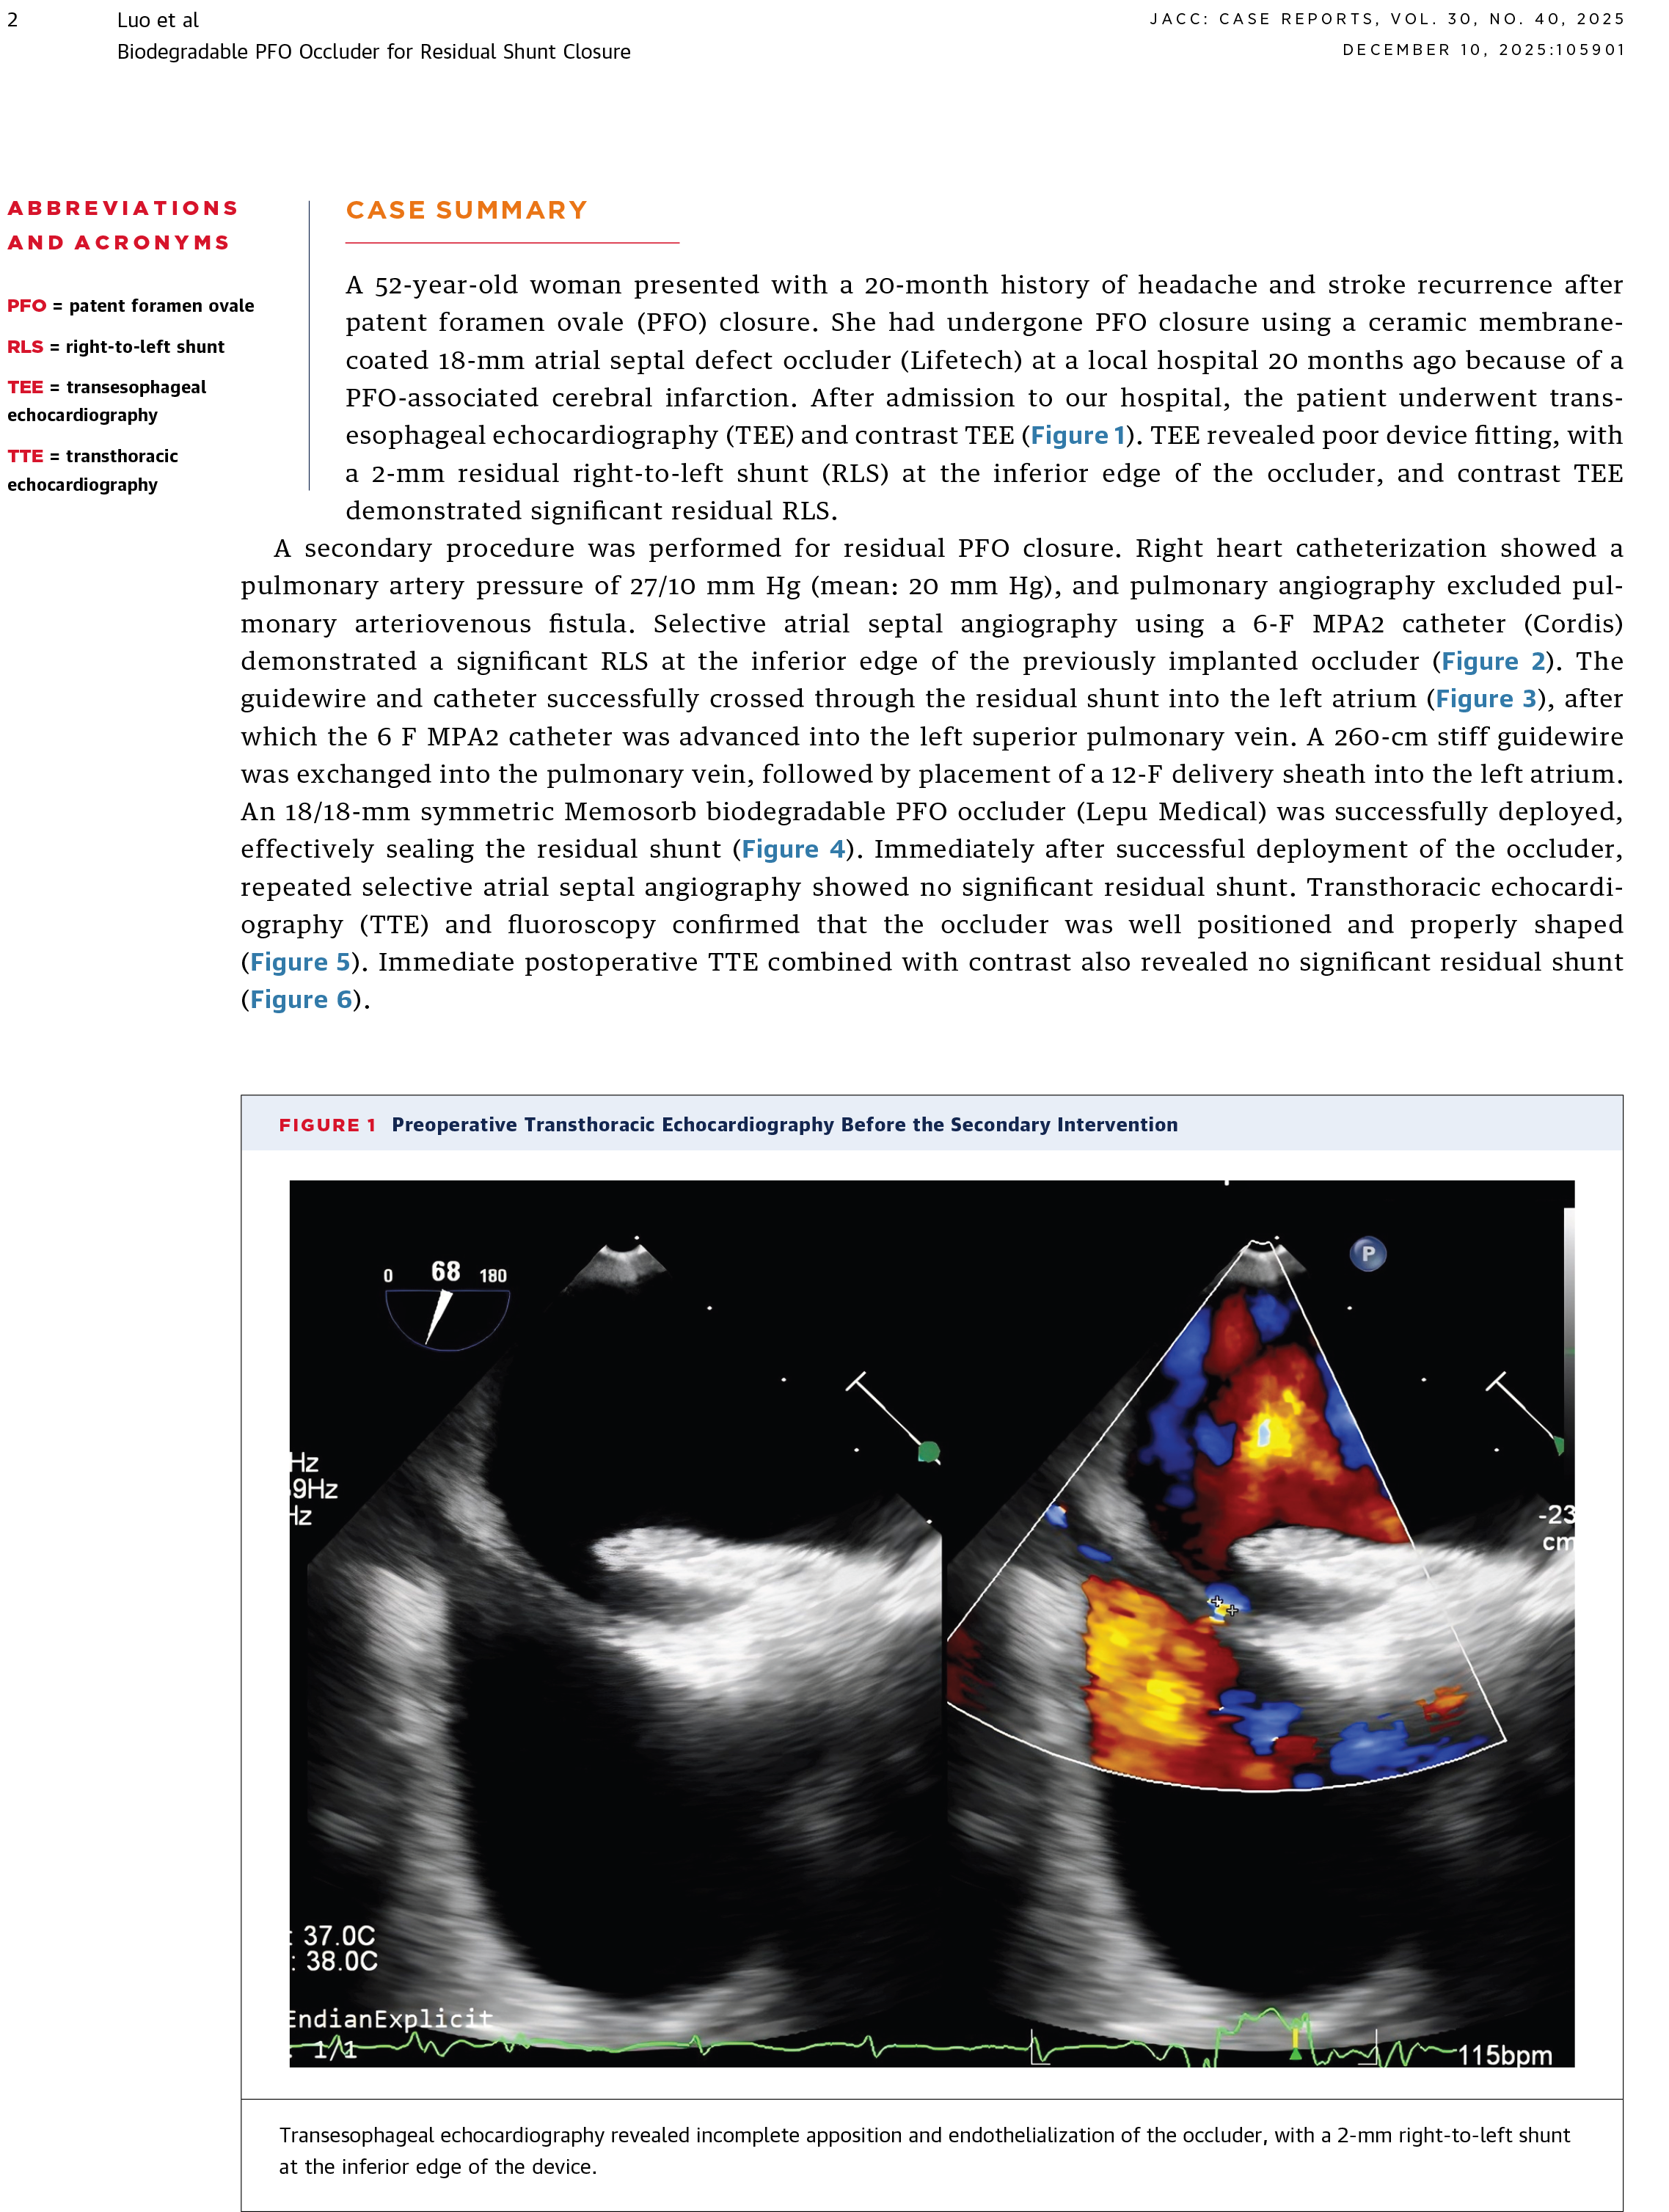

Percutaneous Closure of Residual Shunt After Patent Foramen Ovale Closure With a Biodegradable Occluder